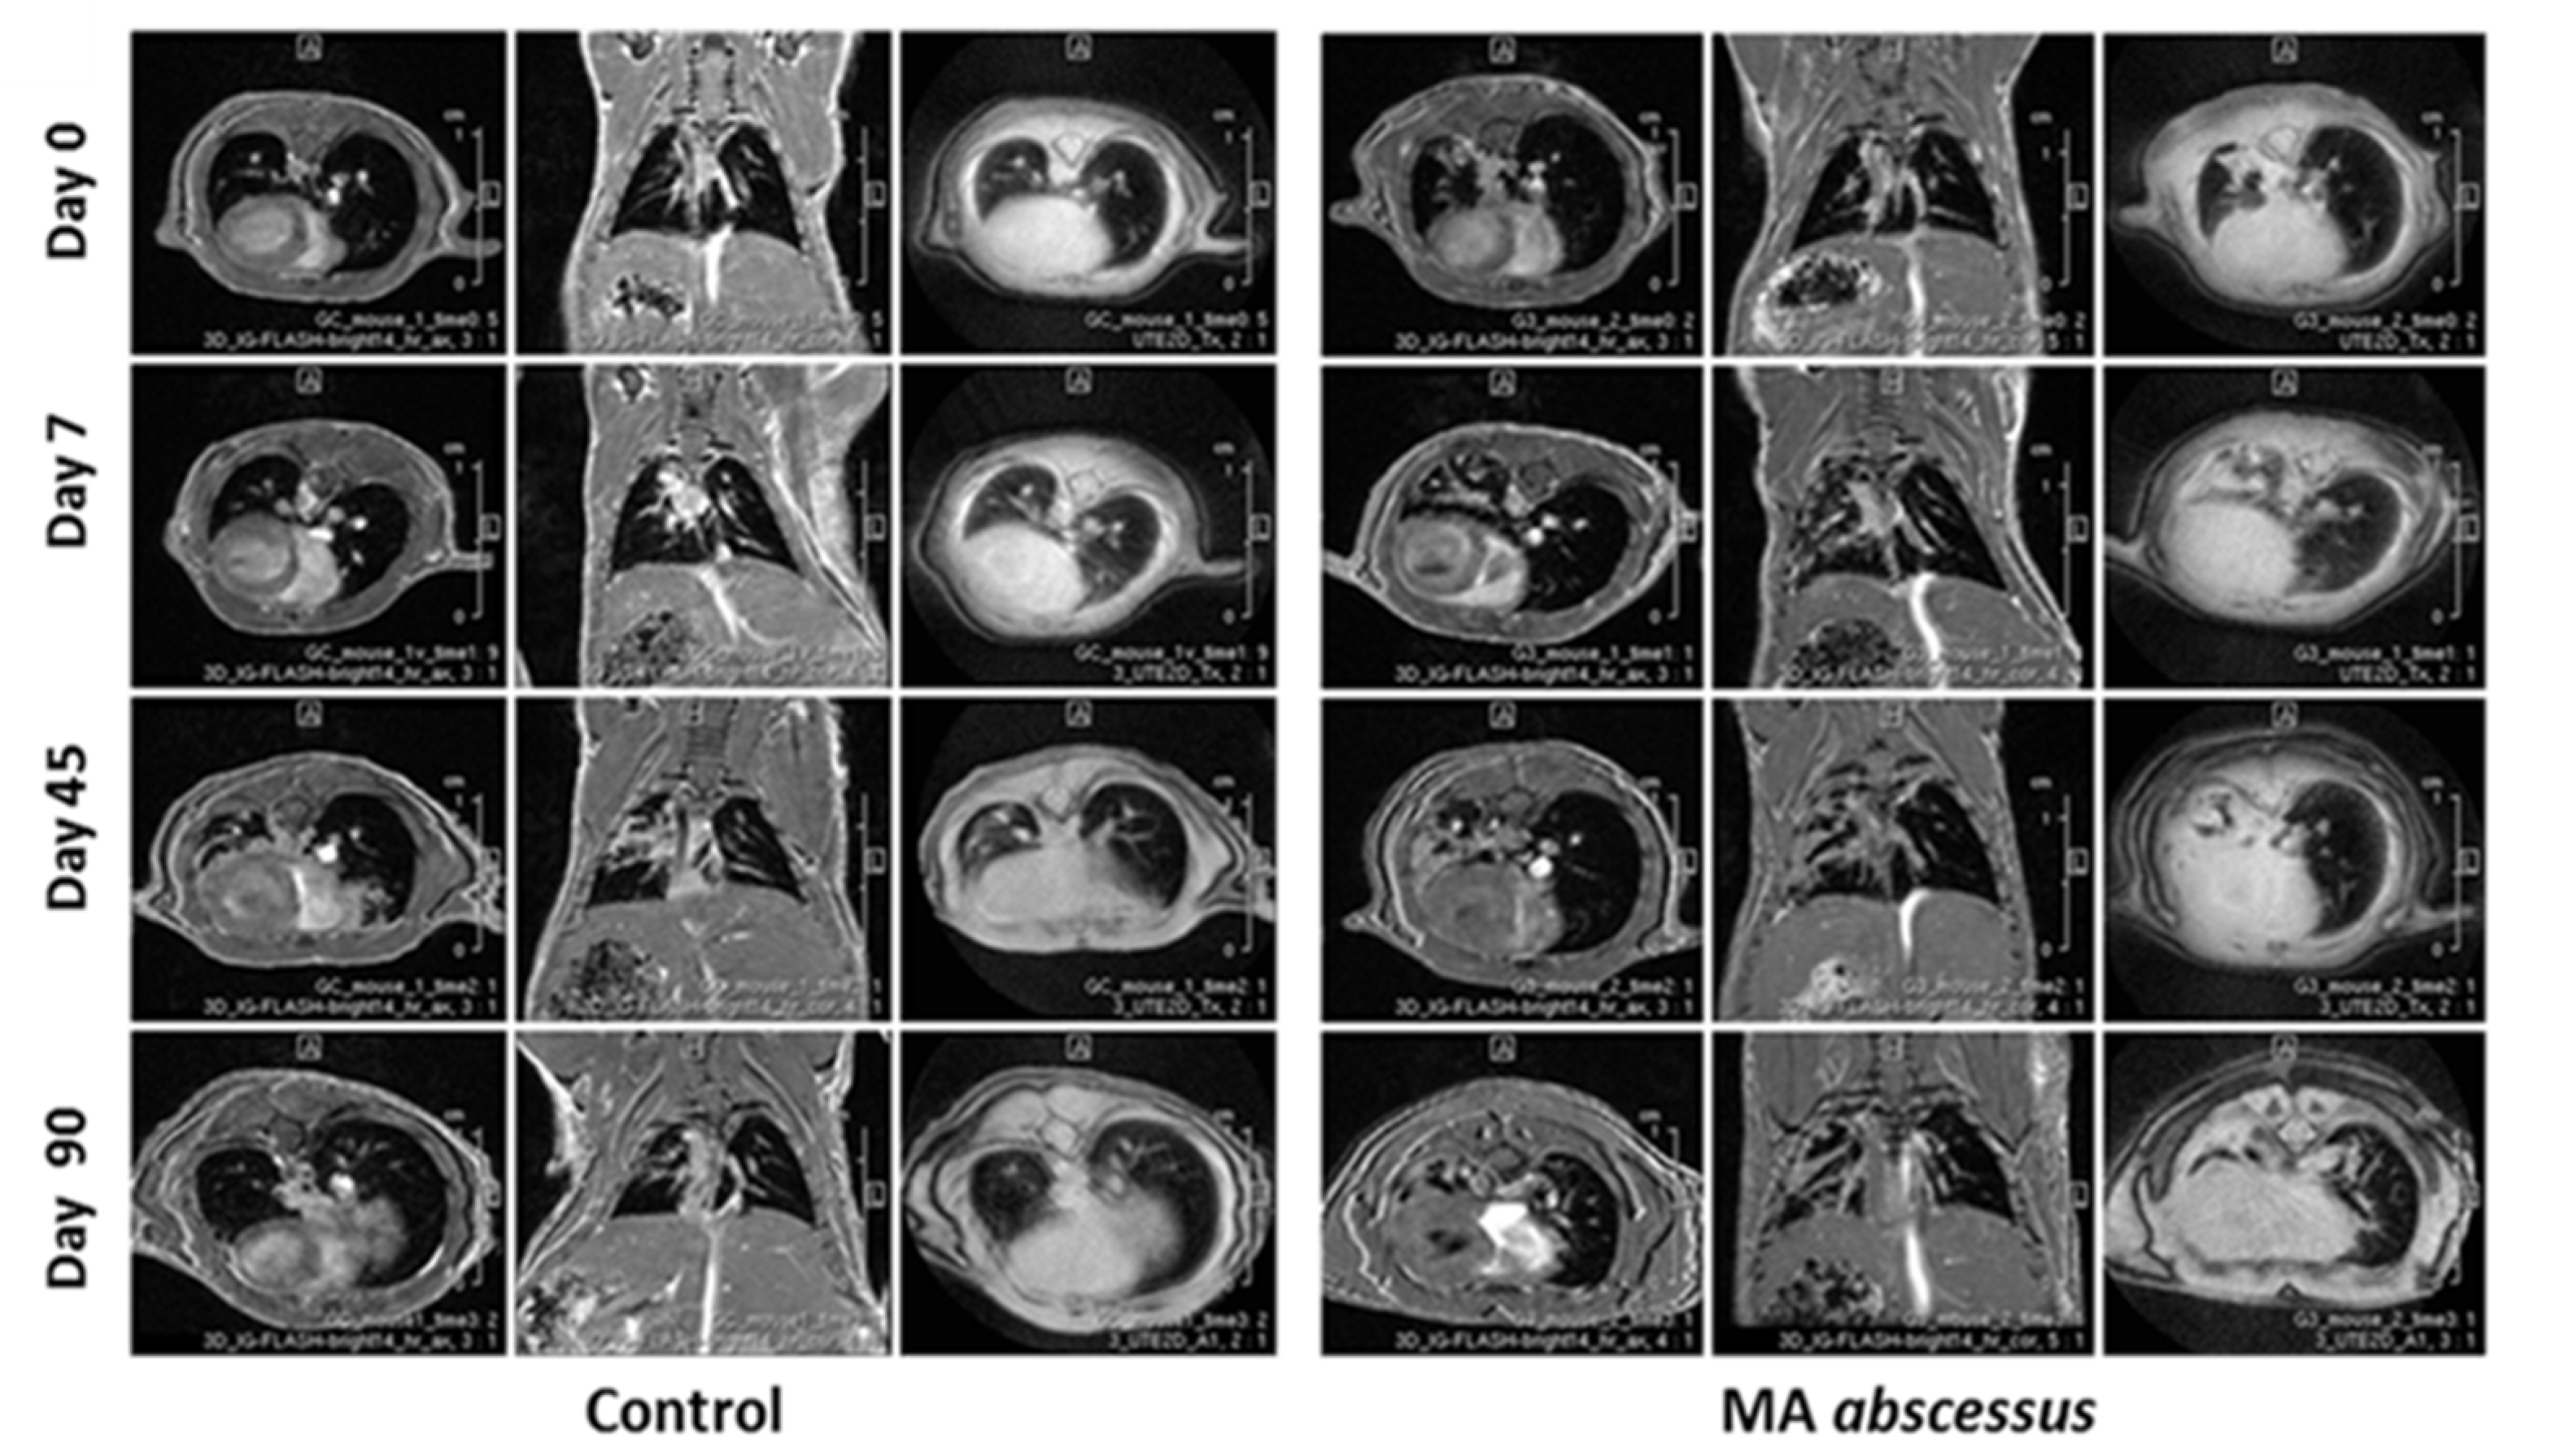

2.1. Chronic Lung Persistence of MA in C57BL/6NCrl Mice

2.2. Lung Lesions and Inflammatory Response during MA Chronic Infection in C57BL/6NCrl Mice

4.6. MRI Longitudinal Monitoring

4.7. Image Analysis